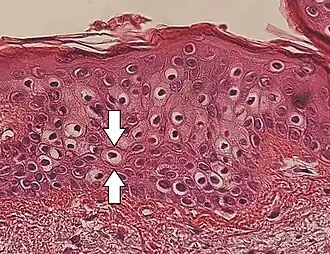

Vacuolization is the formation of vacuoles or vacuole-like structures, within or adjacent to cells. Perinuclear vacuolization of epidermal keratinocytes is most likely inconsequential when not observed in combination with other pathologic findings. In dermatopathology "vacuolization" often refers specifically to vacuoles in the basal cell-basement membrane zone area, where it is an unspecific sign of disease.[1] It may be a sign of for example vacuolar interface dermatitis, which in turn has many causes.

It is one of the components of koilocytosis, which may be present in potentially pre-cancerous cervical, oral and anal lesions.[2]